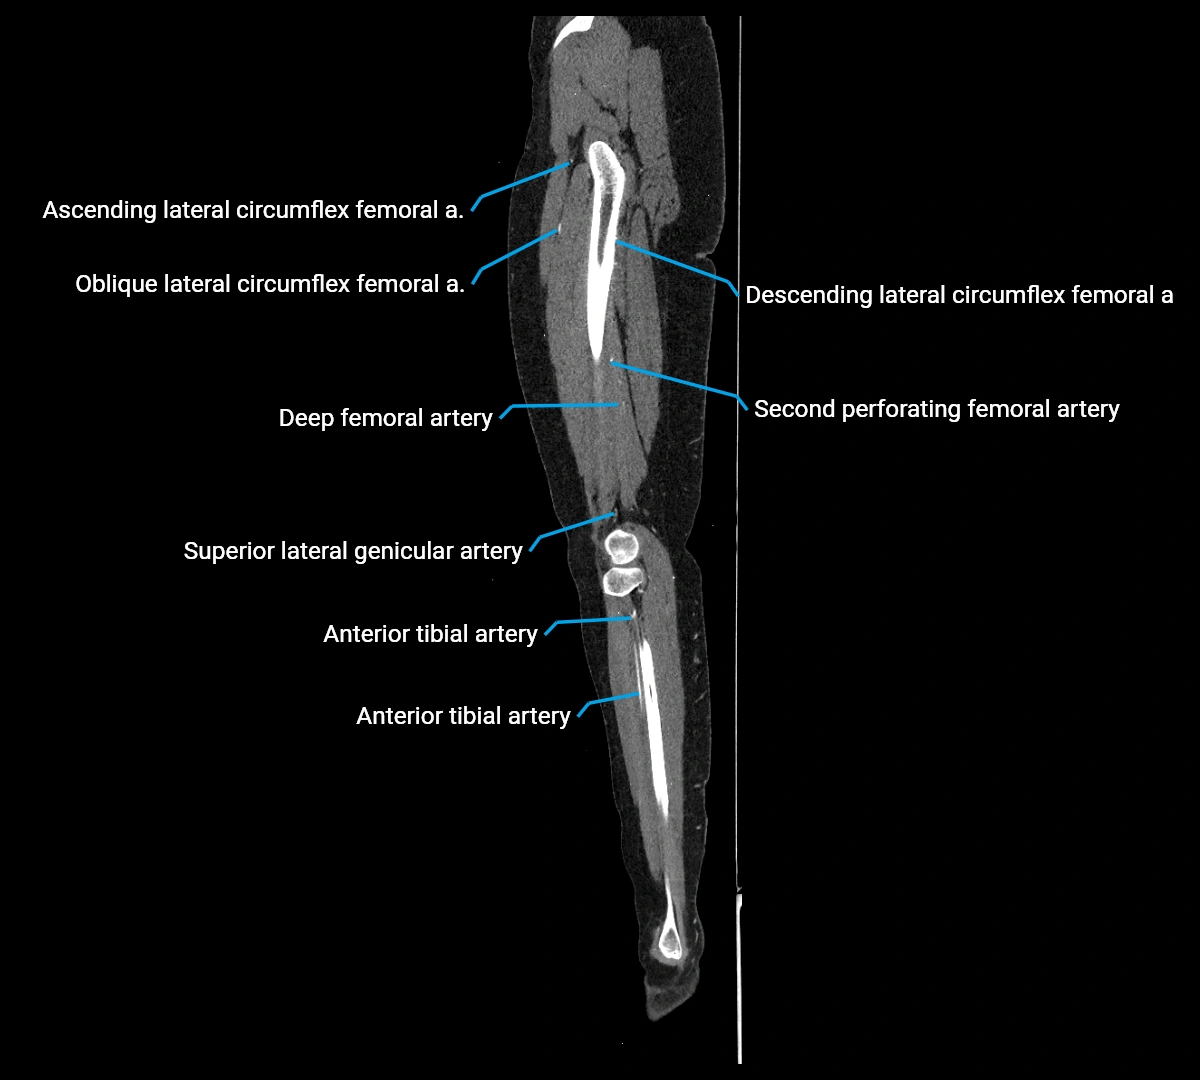

CT images

image